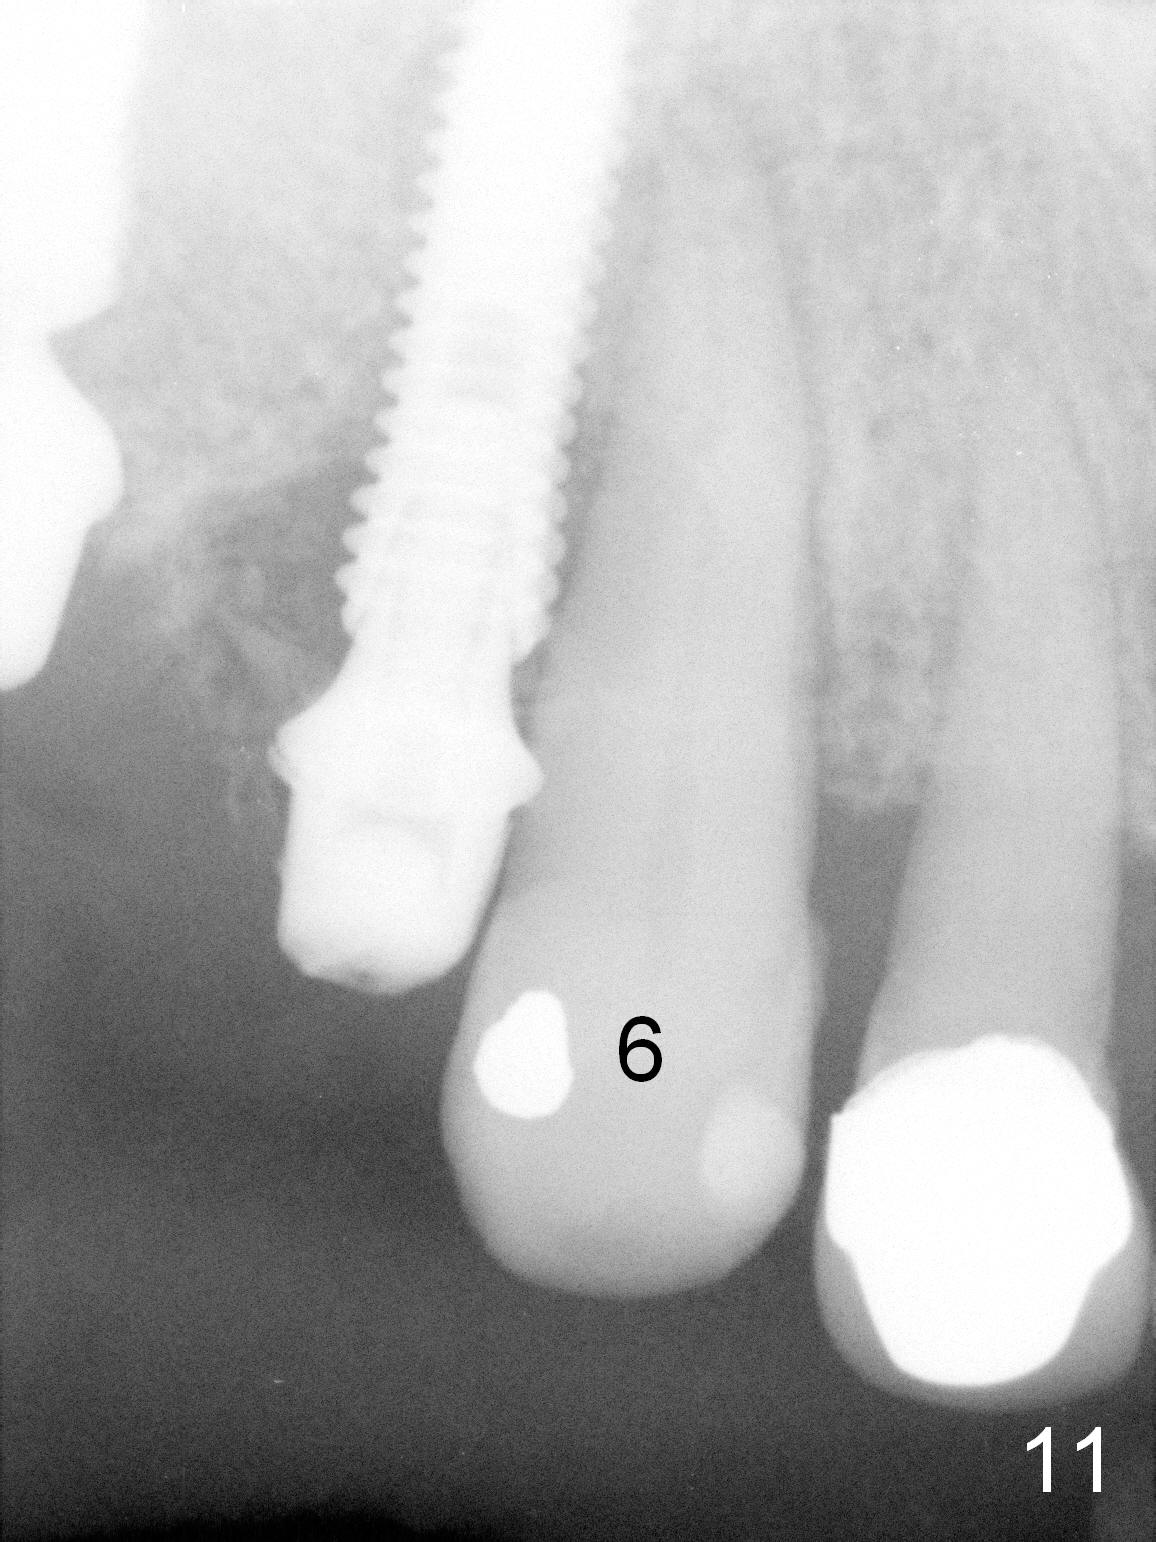

There is no infection around the implants 1 months postop (Fig.9,10). In fact infection mesial to #6 is more severe than preop (Fig.9 arrowhead, Fig.11). When the provisionals are removed for trimming, there is yellowish bone graft around the abutments, which is apparently not incorporated by the body (Fig.9,10 *). It is easily removed by spraying water. The margin of the abutment at #5 is subgingival; an abutment with a longer cuff should be changed next visit.

Although the patient feels better after taking Amoxicillin, the infection remains at #6-8 five weeks postop (Fig.12,13). The tooth #8 appears to be extruded with >10 mm buccal pocket. Water pik is recommended. It seems that the teeth #6-8 should be extracted and replaced with implants. Scaling & root planing should be tried first (Fig.11,12).

Two months and a half postop (#3,5 implantation), the patient agrees to have #6-8 to be extracted because of persistent infection. She reports dislodgement of the provisional at #3-5 using water pik. The provisional is found to be mobile. PA shows decrease in bone density around the implant at #5, probably due to proximity to the infection (Fig.14 *).